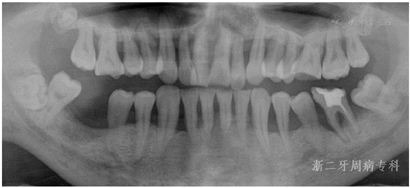

全口曲面体层X片示:全口牙槽骨广泛性水平吸收,46牙槽骨吸收超过根尖;36根尖周和根分叉区低密度影;13、22、23、33~35、43~45、47牙槽骨吸收达根长1/2~2/3,余牙牙槽骨吸收至近根尖(图3)。